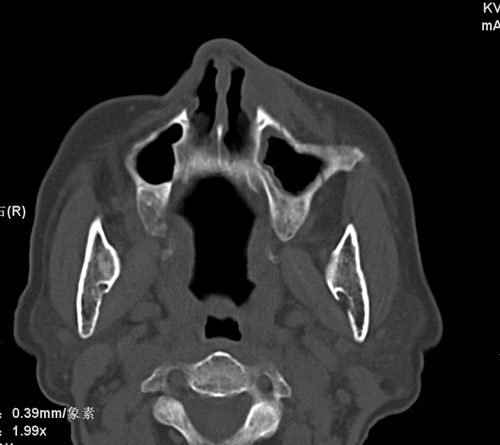

标题: CT17755:女,74 左鼻旁肿胀半年,临床以左上颌窦旁占位行CT [打印本页]

标题: CT17755:女,74 左鼻旁肿胀半年,临床以左上颌窦旁占位行CT

ct考虑鼻前庭囊肿 或鼻翼基底部慢性炎症,左上颌窦少许炎症 请指教

1)考虑左侧鼻前庭囊肿并感染。2)双侧上颌窦炎。

左侧鼻前庭囊肿并感染。双侧上颌窦炎。支持